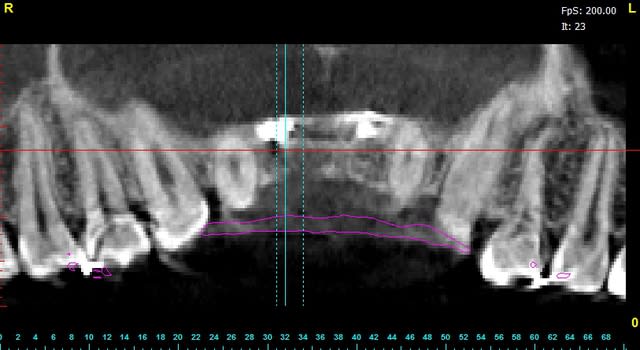

la suite demain matin...

enfin, dans quelques heures...

Pour les non-initiés, mon 57, tes photos sont tres belles, mais ca manque un peu de texte et d'explications, non?. Tu as fait plus didactique!

Sorry D57 , mais il me semble que la pose des implants est tout à fait possible en première intention. la configuration anatomique est tout à fait favorable à une ROG classique sur les implants avec ou sans vis supplémentaire.

pourquoi faire compliqué ?

Je crois bien que tu vas pouvoir faire une petite expansion, sur greffe biobank, il me semble que j'ai déjà vu ça et que ça marche...;-))